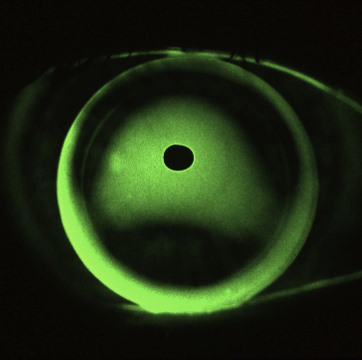

Contact lens technology is advancing too, with the larger corneo-scleral and scleral rigid contact lens being the hot topic in specialty lens circles these days. Many will extol the virtues of vaulting over the irregularity of a corneal graft with a large rigid lens. However, I believe that corneal grafts are one condition for which scleral rigid lenses should be used with caution. This is mainly due to the potential for hypoxic and physiological stress these lenses can induce to an unstable and fragile tissue (Fig 1). Don’t forget that endothelial cell counts are typically reduced post-keratoplasty, reaching levels of 865 cells/mm2 after 10 years in one study, a decrease of 61% from pre-surgical levels¹. A scleral lens design that will be perfectly adequate for a healthy keratoconic eye may provide insufficient oxygen in an older graft. Oxygen is not everything either, with many scleral lens experts internationally believing that limbal insult can cause just as many complications as hypoxia. Scleral lenses certainly have their place but always require careful design and relentless follow-up.

It is my belief that a well-fitted corneal rigid lens provides the best first choice for most corneal grafts. Corneal lenses offer great improvements in vision with acceptable comfort and generally a low effect on corneal physiology, hopefully facilitating a number of years of successful use.